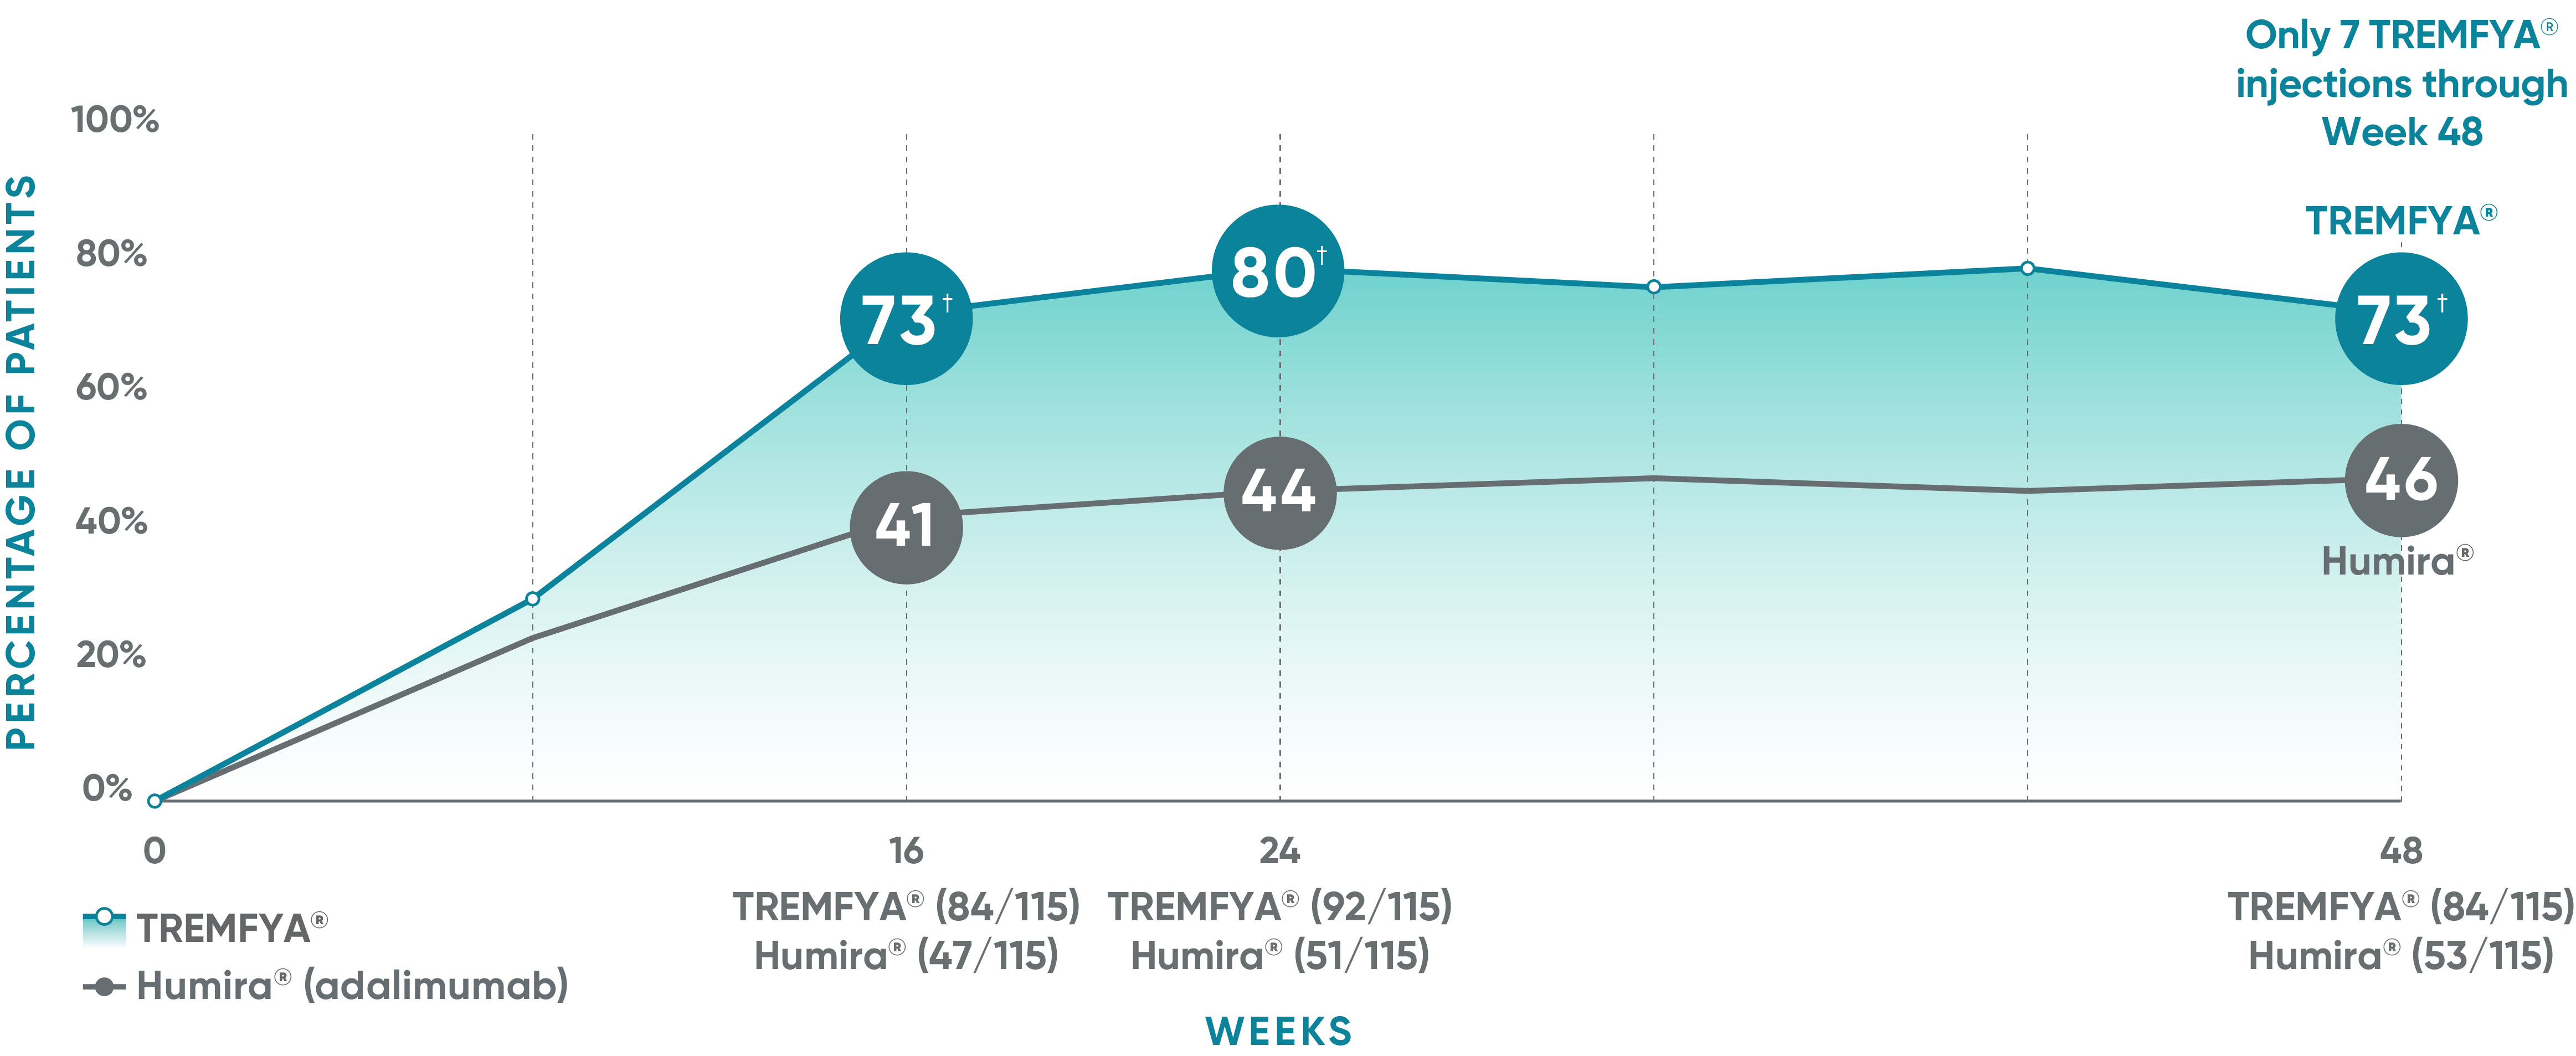

VOYAGE 1: Major secondary endpoints PASI 90 response at Weeks 16, 24, and 48 (NRI)*

The same patients may not have responded at each time point.

VOYAGE 2: Major secondary endpoint at Week 16 (NRI)1,2*†

- 64% (102/160) of patients receiving TREMFYA® achieved PASI 90 vs 42% (34/81) of patients receiving Humira®

VOYAGE 2: Major secondary endpoint at Week 24 (NRI)1,2*‡

- 71% (113/160) of patients receiving TREMFYA® achieved PASI 90 vs 51% (41/81) of patients receiving Humira®

*Results from North American sites only, which used US-licensed Humira®.

†P<0.001 vs Humira®.

‡P=0.003 vs Humira®.

Consistent efficacy, dose to dose

VOYAGE 1: Prespecified secondary analysis—PASI 90 response rates through Week 48 (NRI)1,2

Data shown include patients randomized at Week 0 to the TREMFYA® arm.

The same patients may not have responded at each time point.

Placebo and active-comparator data are not shown in chart.

VOYAGE 2: PASI 90 at Weeks 16 and 24 (major secondary endpoints, NRI)3*

- 64% (102/160) of patients receiving TREMFYA® achieved PASI 90 response at Week 16

- 71% (113/160) of patients receiving TREMFYA® achieved PASI 90 response at Week 24

*Results from North American sites only, which used US-licensed Humira®.

Dosing and administration

- 100 mg administered by subcutaneous injection at Week 0, Week 4, and every 8 weeks thereafter3